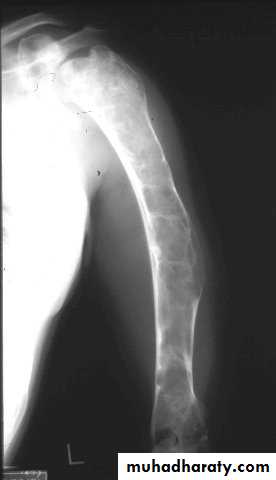

Developmental disorder whereby normal bone is replaced by fibrous tissue with flecks of osteoid.It may affect one bone (monostotic) or multiple bones (polystotic).

The lesion may be very large causes bone expansion and cortical thinning with progressive deformity and sometimes pathological fracture.Lesions occur in metaphysis & diaphysis, proximal femur is a common site it gives characteristic deformity called (shepherd’s-crock deformity(عصا الراعي.

X-ray shows lucent cystic lesion sometimes large and multilocular with bone expansion and cortical thinning it contains multiple calcific spots giving the ground-glass appearance, there is always possible deformity or pathological fracture.